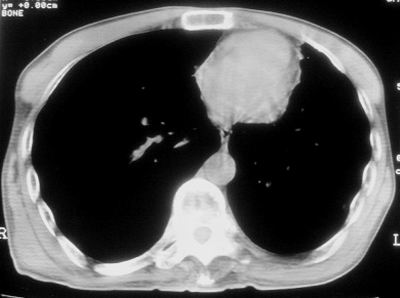

标题: CT11864:男,47岁,反复咳嗽、咯痰、咯血3年,请分析. [打印本页]

标题: CT11864:男,47岁,反复咳嗽、咯痰、咯血3年,请分析.

患者,男,47岁,反复咳嗽、咯痰、咯血3年,再发5天。痰培养未找到真菌、抗酸杆菌、癌细胞。

左肺上叶体积明显缩小,其内见多发透光区,纵隔向左侧移位,左肺下叶多发班片状病灶,边界模糊,1左肺上叶先天肺发育不全,2左肺下叶肺炎,

左肺上叶结核伴肺纤维化,纵隔移位,左肺下叶感染性病变,建议抗炎抗结核后复查,双肺气肿.

以下是引用xulianj在2008-2-25 21:01:00的发言:[br]左肺上叶结核伴肺纤维化有霉菌球形成,纵隔移位,左肺下叶感染性病变,建议抗炎抗结核后复查,双肺气肿.

考虑:左肺慢纤伴霉菌球形成、双肺全小叶型肺气肿。

1)考虑为:左肺上叶肺结核(空洞形成),伴左下肺感染;不排除霉菌感染可能。2)肺气肿。

左肺上叶结核伴肺纤维化空洞形成并左肺下叶感染,纵隔牵拉移位,建议作进一步检查排除左侧肺霉菌感染可能。